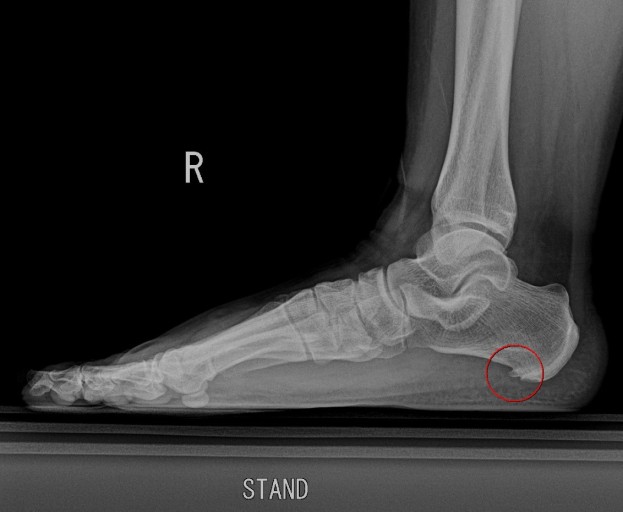

족저근막염 치료방법

인터넷을 찾아봐도 족저근막염에는 특별한 치료법이 없는 것 같다. 체외충격파를 이용하는 사람들도 있던데 개인적으로는 별 효과가 없는듯 했다. 족저근막염을 개선하기 위한 단순한 방법이 있다.

발을 잘 지지해줄 수 있는 편안한 신발을 신고 정상체중까지 체중을 감량하며 사무실이나 집에서는 틈틈이 발바닥 스트레칭을 해준다. 가급적 방바닥을 맨발로 걸어다니지 말고 굽이 두껍고 푹신한 슬리퍼를 착용해서 무게를 분산시키는게 좋다.